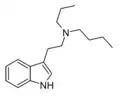

| DPT | artificial | H | CH2CH2CH3 | CH2CH2CH3 | N,N-dipropyltryptamine | 61-52-9 |